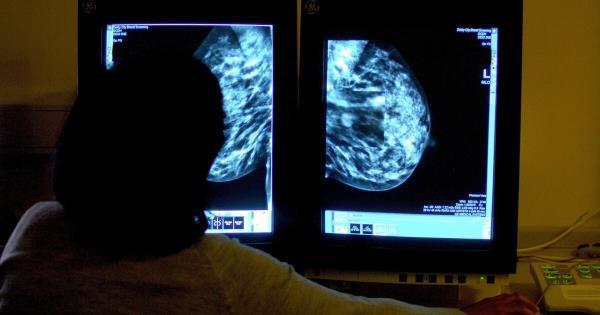

【健康警报】26%!年轻女性乳腺癌发病率激增,30+的你一定要看!

:当我们在社交媒体上刷着美食与旅行照片时,一组冰冷的数据正在敲响健康警钟——爱尔兰20-49岁女性乳腺癌确诊率十年激增26%!这不仅是医疗报告中的数字...